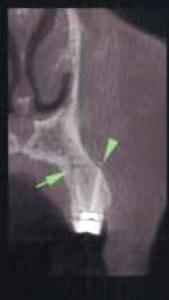

Полость корневых каналов промыли физиологическим раствором и восстановили зуб с помощью материалов для временного пломбирования. Чтобы предотвратить риск инфекции, в течение трех дней внутримышечно пациентке вводили клиндамицин (600 мг дважды в день), и также назначили ибупрофен (400 мг) для купирования боли, который она принимали по мере необходимости. Экстренное наружное использование холодных компрессов в первый день сменили на теплые компрессы во второй день для лечения отека. На первом повторном визите отмечалось увеличение кровоподтека, хотя припухлость значительно уменьшилась (фото 3). Отек и кровоподтек постепенно исчезали в течение всего периода наблюдения, а на 10 день после процедуры у пациентки исчезли все беспокоившие ее симптомы (фото 4). Для оценки соотношения между зубом, альвеолярным отростком и верхнечелюстной пазухой была проведена дентальная объемная томография (dental volumetric tomography — DVT) (NewTom 3G, QR SRL, Верона, Италия). На DVT-изображении было обнаружено, что апекс щечного корня перфорирует кортикальную пластинку верхнечелюстной кости, создавая, таким образом, свободный путь для проникновения ирригационного раствора в мягкие ткани (фото 5 (а) и фото 5 (б)). Через 10 дней симптомы полностью исчезли. В то же время в корневой канал наложили повязку с гидроксидом кальция. Во время заключительного посещения примерно через 4 недели после предыдущей процедуры корневые каналы запломбировали материалом AH Plus (Dentsply Maillefer) и гуттаперчей (фото 6).

Фото 5: (а) Изображение 3D и (б) коронарный вид DVT показали, что верхушка щечного канала перфорирует кортикальную пластинку верхней челюсти.

Большинство случаев выведения NaOCl за верхушку корня возникают вследствие неправильного определения рабочей длины инструмента, чрезмерного расширения апикального отверстия, боковых перфораций, заклинивания иглы в корневом канале или же вертикальных переломов корня. Деструкция альвеолярной кости в периапикальной области из-за присутствующих хронических инфекций, как и использование высокого давления во время инъекции только способствуют процессу экструзии NaOCl-ирриганта в окружающие мягкие ткани. В ходе анализа 23 случаев определено, что 18 пациентов были женщинами, а остальные 5 – мужчинами, 20 инцидентов случилось на верхней челюсти, и только 3 на нижней. Это можно объяснить тем, что зубы нижней челюсти расположены в центре более плотной кортикальной кости по сравнению с верхними зубами. Тонкий слой кортикальной пластинки внешне ограничивает область щечного корня премоляра верхней челюсти и остальных коренных зубов. Таким образом, зубы верхней челюсти более предрасположены к экструзии NaOCl в окружающие мягкие ткани по сравнению с зубами нижней челюсти. Behrents и коллеги также сообщили, что экструзия гипохлорита натрия возможна и при обработке корней второго премоляра верхней челюсти. На изображениях конусно-лучевой компьютерной томографии (КЛКТ) видно, что в данном клиническом случае верхушка щечного корня перфорировала кость верхней челюсти. Также в данном случае изображения DVT продемонстрировали, что существующая ранее периапикальная хроническая инфекция, как и перфорация верхнечелюстной кости верхушкой щечного корня, способствовали экструзии NaOCl. Кроме того, более чем вероятно, что врач применял избыточное давление при манипуляциях с ирригационной иглой или же иглу заклинивало в корневом канале, что также негативно повлияло на будущий прогноз неадекватной обработки канала. Более того, следует помнить, что в сомнительных случаях начальная томография может помочь определить возможные факторы риска, способствующие экструзии NaOCl.